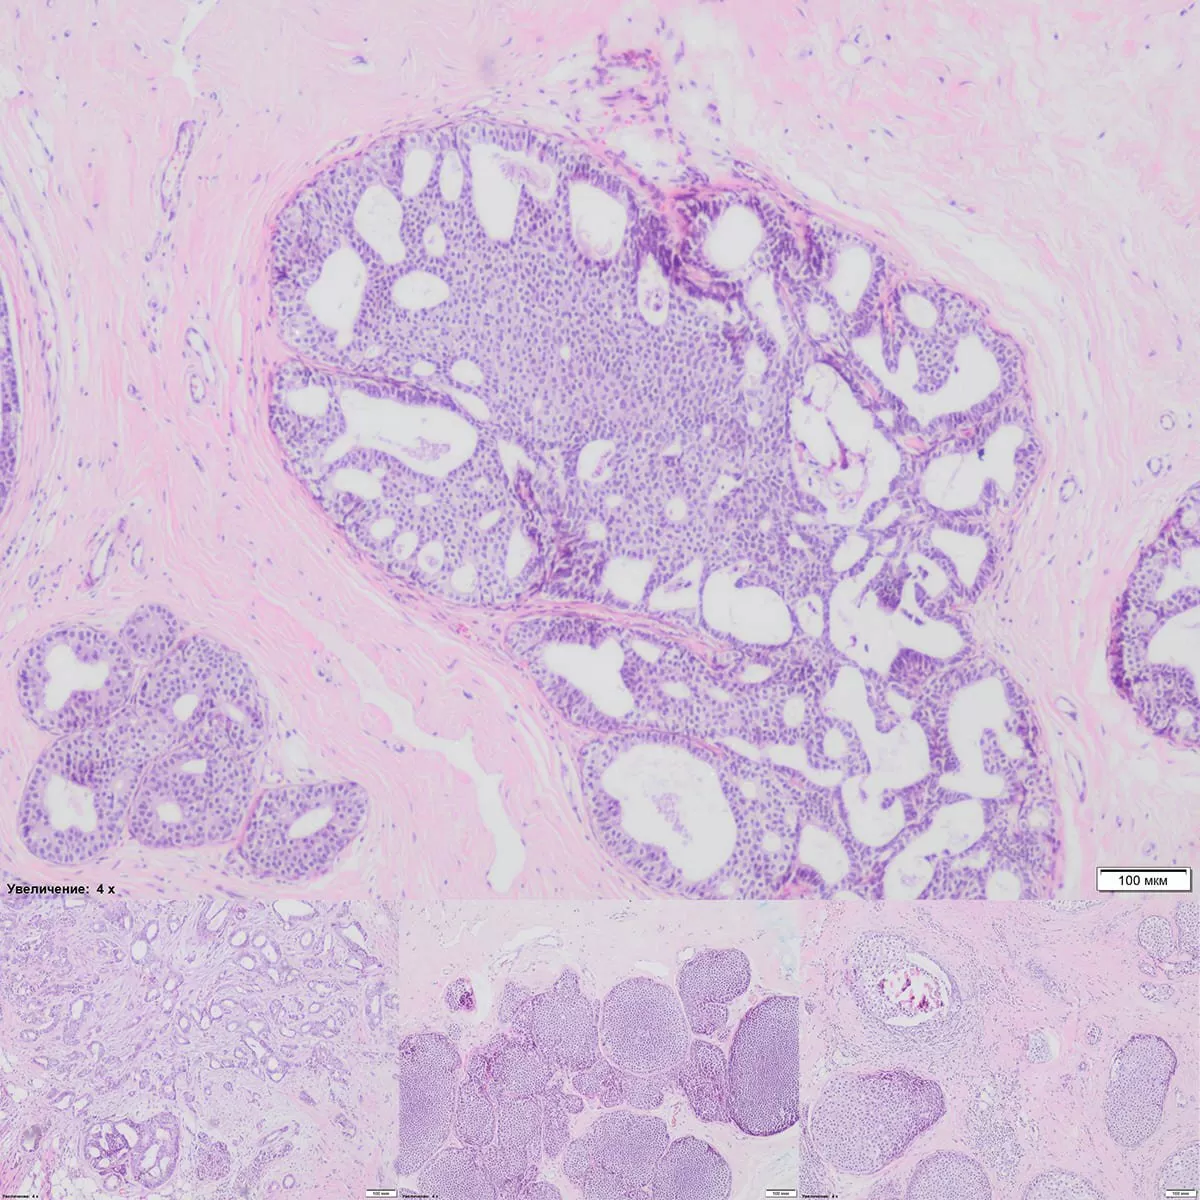

Через несколько дней получены результаты гистологического и иммуногистохимического исследования биоптата: Умеренно дифференцированная G2 инвазивная неспецифицированная карцинома правой МЗ cT1 cN0 MОER+++, PR+++, HER-2/neu+; Ки-67 – до 15%. Мутации исключены.

Финально маммографические размеры опухоли – 3 мм, гистологические – 6 мм. Это первая, ранняя стадия, рак in situ, промежуточной степени злокачественности, тип ER+++, PR+++, Her-2/neu+, который имеет хороший прогноз дальнейшей жизни пациентки. Индекс Ki-67 низкий, что также, как биомаркер пролиферации, подтверждает надежду на выздоровление от рака МЗ.